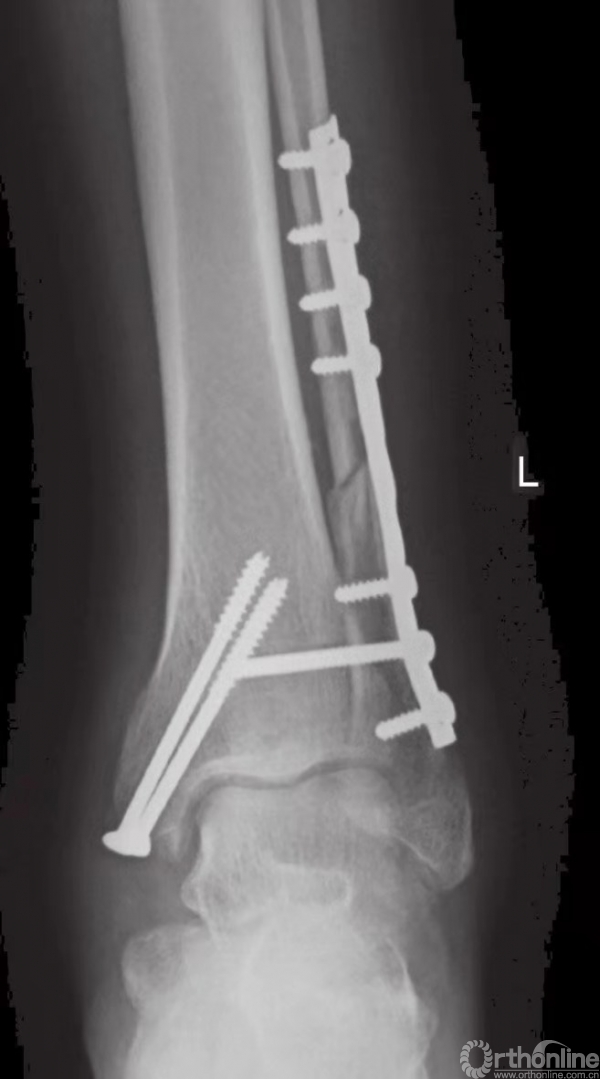

外踝固定技术

腓骨远端为皮下骨骼,因此应避免以腓骨远端为中心直接切开成口。一般在腓骨远端的后外侧表面切口(图2),这样就避免了伤口张开或裂开时接骨板暴露。如果因粉碎性骨折和Pilon骨折而要在踝关节前方开口,上述切口也可与该切口保持足够的距离。

清理骨折末端软组织后,借助小复位钳将骨折片复位(图4)。解剖复位和腓骨长度的保持,尤为重要。除了腓骨的长度之外,也应检查旋转的方向。腓骨的短斜形骨折可用一枚拉力螺钉和一块中和接骨板加以固定(图5~8)。

长螺旋形骨折可用两枚拉力螺钉和一块中和接骨板加以固定。骨折线的两侧最少须四皮质固定。较小的1/3或半形管状接骨板通常用于固定腓骨。3.5mm的动力性加压接骨板也被用于体型较大的患者。近期,用于腓骨固定的特制接骨板也被研发出来。

当发生腓骨粉碎时,使用桥形接骨板,从而能绕过碎骨,皮质固定也可在骨折区域上下完成。在用螺钉固定前,应预先描出接骨板的轮廓。有时,如果在很低的位置发生横行骨折,可在踝部用4mm的张力性钢丝带加以固定。术中进行影像学检查,可以极为有效地避免远端的螺钉将关节刺穿(图9)。

下胫腓联合固定技术

在完成所有踝部骨折的固定之后,应评估下胫腓联合的稳定性。如果下胫腓联合关节上方或下胫腓联合水平发生腓骨骨折,应充分检查下胫腓联合的稳定性。在前后和中外两个平面上,应检查其完整性(图23)。另外,因为下胫腓联合发生损伤时腓骨可能向外旋转,故还应检查腓骨的旋转情况。

如果下胫腓联合不稳,则须进行固定,固定时采用皮质骨螺钉。由于腓骨在解剖关系上位于胫骨的后外侧,因此应将螺钉从后向前以30°的角度嵌入。一般认为,三皮质骨螺钉固定足以保证下胫腓联合的稳定性。螺钉应至少高过关节线2cm(图24和图25)。

图25 通过钢板的皮质骨螺钉固定旋前外旋型下胫腓联合损伤